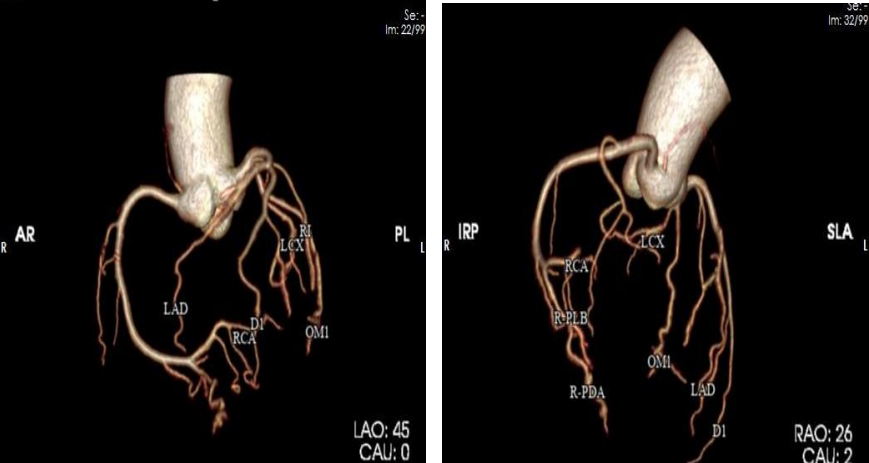

我院放射科通过 CT 联影 UCT-710

成功开展

首例冠脉动脉 CT 血管造影(CTA)检查

填补了我院在此项技术的空白

此种方法是将造影剂通过静脉途径以 4-6ml/s 的速度输入患者体内,利用人工智能、软件智能跟踪及心电门控等技术,对冠状动脉及其分支,心脏室壁运动等进行清晰显示。与传统冠脉造影相比,冠脉 CTA 对于冠脉开口变异,能更好地显示血管的开口情况,更好地确定冠脉斑块的性质, 并能显示冠脉以外的病变:如心肌桥、肿瘤等,对心脏和大血管解剖结构的显示优良。

CT具有成像速度超快、图像清晰的优点,能够开展各器官脏器平扫、增强检查、全身血管造影剂灌注成像检查,具有二维、三维等多种重建技术及丰富的影像后处理软件;能够开展CT全身血管成像、冠状动脉血管成像、全身多部位大血管联合成像、胸痛及卒中一站式检查、全身多脏器血流灌注成像,能谱CT成像,达到对冠心病、急性脑卒中、心肌梗死等疾病的早期诊断。熟练开展CT引导下的穿刺活检、CT引导下腰椎间盘突出症臭氧消融治疗术。